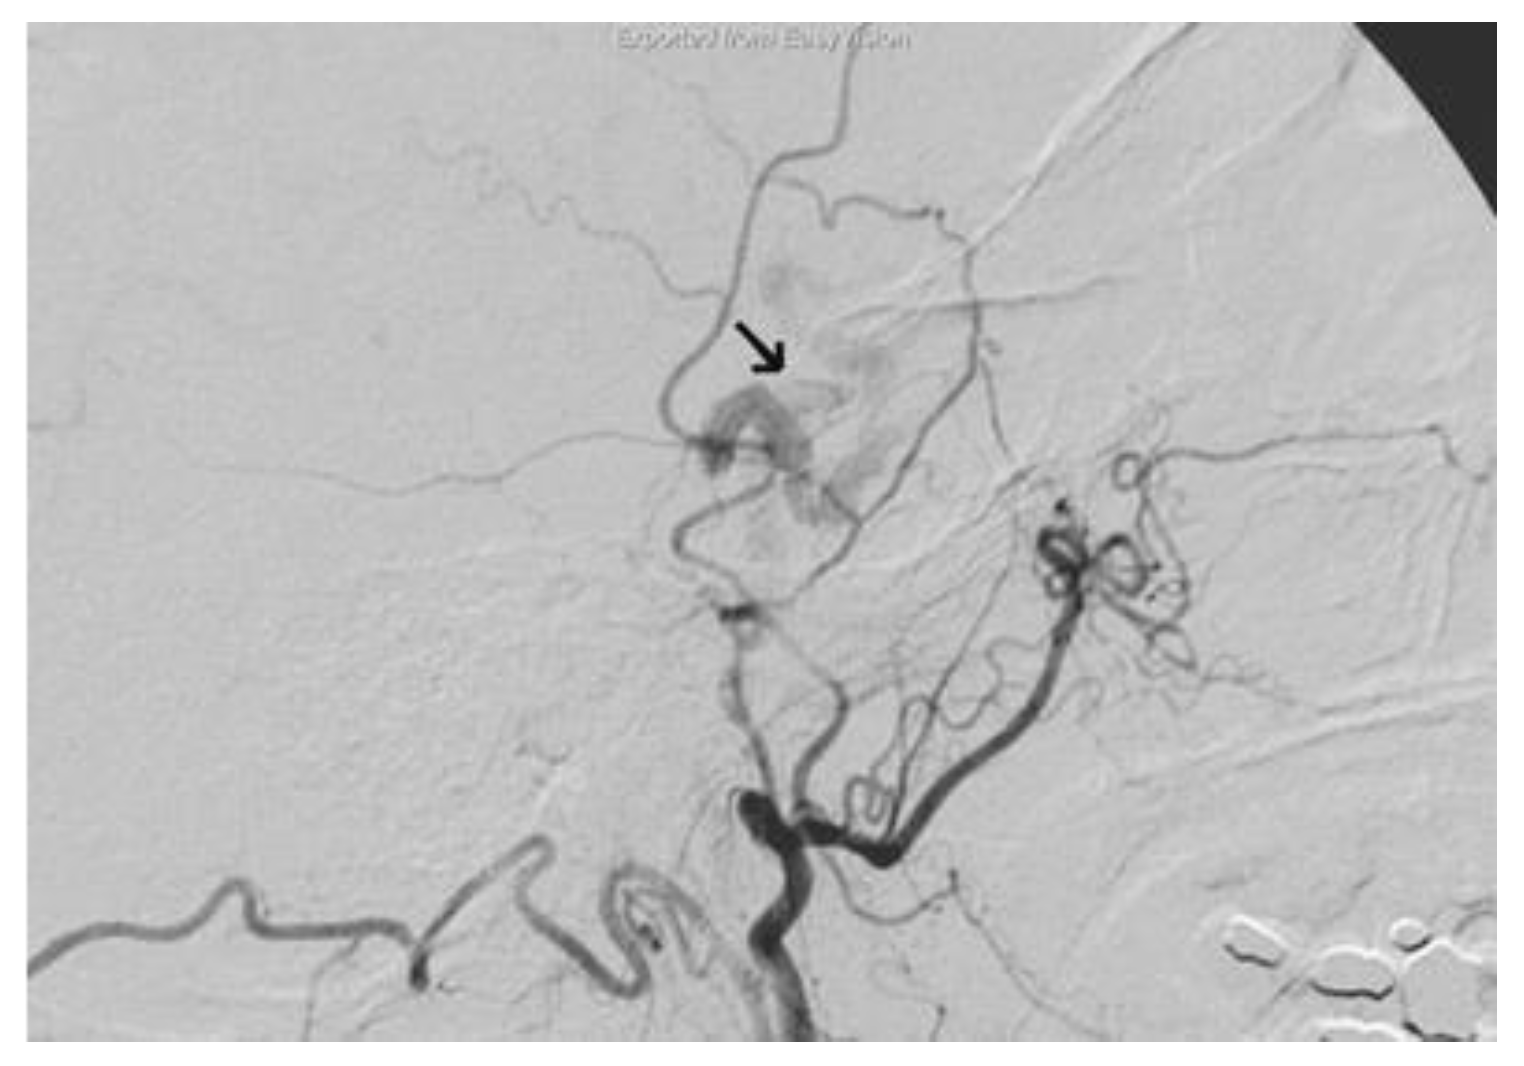

The selective cerebral angiography (Figure 5), carried out through right femoral catheterization, revealed a dural fistula of the right cavernous sinus wall between the branches of the internal maxillary artery, most likely of the accessory meningeal artery, and the cavernous sinus with early opacification of the ophthalmic vein that presented an increased caliber.

Figure 5. The selective cerebral angiography revealing a dural fistula of the right cavernous sinus (arrow).